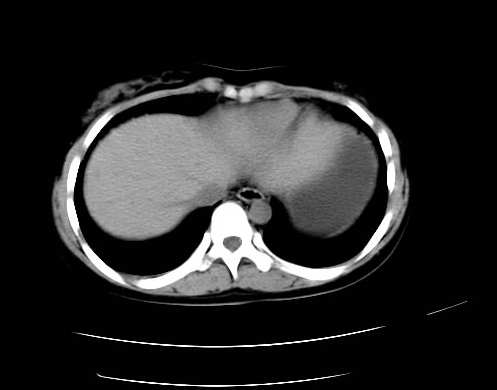

女 16岁  右上腹痛一天,无其他不适

肿块最大径位于十二指肠降段与水平段移行处,并且与肝脏压迹呈“0”形征,可以考虑位于肝外并与胃肠道关系紧密,考虑胃肠道间质瘤(gist)可能较大,须除外神经节起源肿瘤。

肿块与十二指肠关系密切,支持间质瘤诊断.肝脏与结肠均为受压改变.

右下腹巨大肿快,密度不均匀,内见坏死低密度区,边界清楚,与周边胀器明显有分界,未见强化,多考虑来源于间叶组织的良性肿物.

我坚决反对您的观点,该病例定位:横结肠肝曲与升结肠之间的肠系膜及部分肠壁。请看下图:

病灶巨大,少部分向肠腔内生长,大部分向长腔外生长。其密度不均匀,增强显示明显不均匀强化,并见有大片状始终不强化的不规则坏死液化区。虽然病灶中上部形态尚可,病人又如此年轻,但中下部形态、密度、强化特点强烈提示为恶性病灶。综上,我考虑本病例为:恶性胃肠道间质瘤。